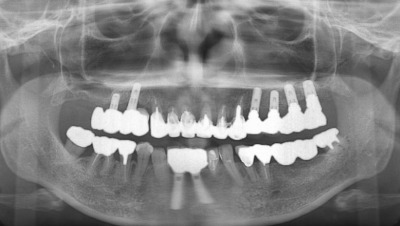

奥歯の噛み合わせが無いインプラント症例の方の治療がほぼ終了しました。

左側上は鼻腔が近くて最初にサイナスリフトをしてその後4本のインプラントを入れました。右側の上はサイナスリフトまではせず、ソケットリフトと歯肉側に少し骨を造るGBRをして2本インプラントにしました。その間に下の前歯にも2本入れて、全体で8本のインプラントとなりました。